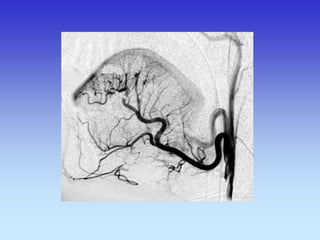

METODE PRIKAZA KRVNIH ŽILA

•UZ-DOPPLER

•DSA

•CTA

•MRA

B-mod i obojeni Doppler karotidne arterije

VASKULARNA OPSKRBA WILLIS-ijev prsten

a. cerebri ant.

a. cerebri media

a. cerebri post.

VASKULARNA OPSKRBNA PODRUČJA